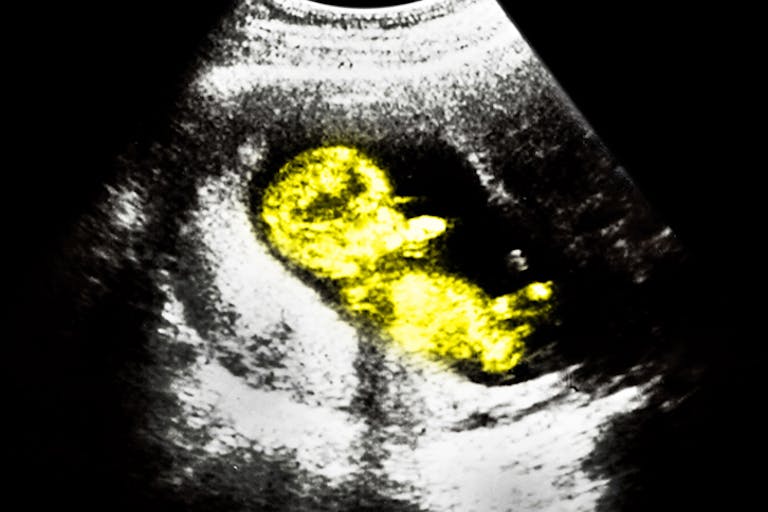

The Times of Israel reports that a new “handheld ultrasound device” is in its finishing stages. It will “allow pregnant women to check on the health of their baby” by connecting to a smartphone. Created by PulseNmore LTD, this device is really designed to provide peace of mind to expectant mothers, as it “display[s] the images on its screen and send[s] them to the pregnant woman’s personal doctor for examination.”

Prof. Israel Meisner of Rabin Medical Center stated that “Women sometimes don’t feel movement, call their doctor and are told to go to an emergency room. Here there’s the option to put a phone on her stomach and see her baby.” This, the designers believe, could cut down on ultrasound costs for this reason. The device is not meant to be used as a diagnostic tool. While not yet fully approved in Israel, the company notes that the device “has been successfully tested in the United States.”

Of course, pro-lifers can see the benefit of such technology as well. When many women who are considering abortion see their preborn babies on the ultrasound screen, they choose life. This is why the abortion industry isn’t a fan of informed consent laws requiring them to show women their ultrasounds, even though ultrasounds are considered standard procedure before an abortion to find the preborn baby’s gestational age and to rule out an ectopic pregnancy.

But with this new ultrasound device that can show women the reality that their babies indeed have heartbeats (as early as 16 days after conception) and other easily recognizable body parts even early in the first trimester, women could very soon be empowered to see for themselves the truth about the child in the womb.

The device is only designed to be used for up to 25 ultrasound checks, and should retail for around $190, not including the cost of a physician examining the images.